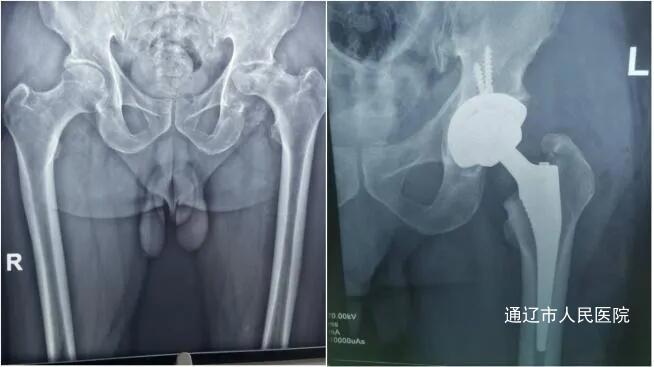

病例2:患者吴某,男性,70岁,1年前开始出现左髋关节疼痛伴活动受限,门诊查体及骨盆X线诊断为:左侧股骨头坏死。胡中申主任医师带领其关节外科团队对该病例进行讨论,针对该患者情况,胡中申主任医师团队在敖日格勒主任医师、文振东主任医师、陈哲主治医师的配合下,为其行“机器人辅助下左侧全髋关节置换术”,不仅实现亚毫米级手术精度,减少了手术创伤,也大大促进了患者的康复进程。术后患者左侧髋关节疼痛明显缓解,功能恢复良好,顺利出院。